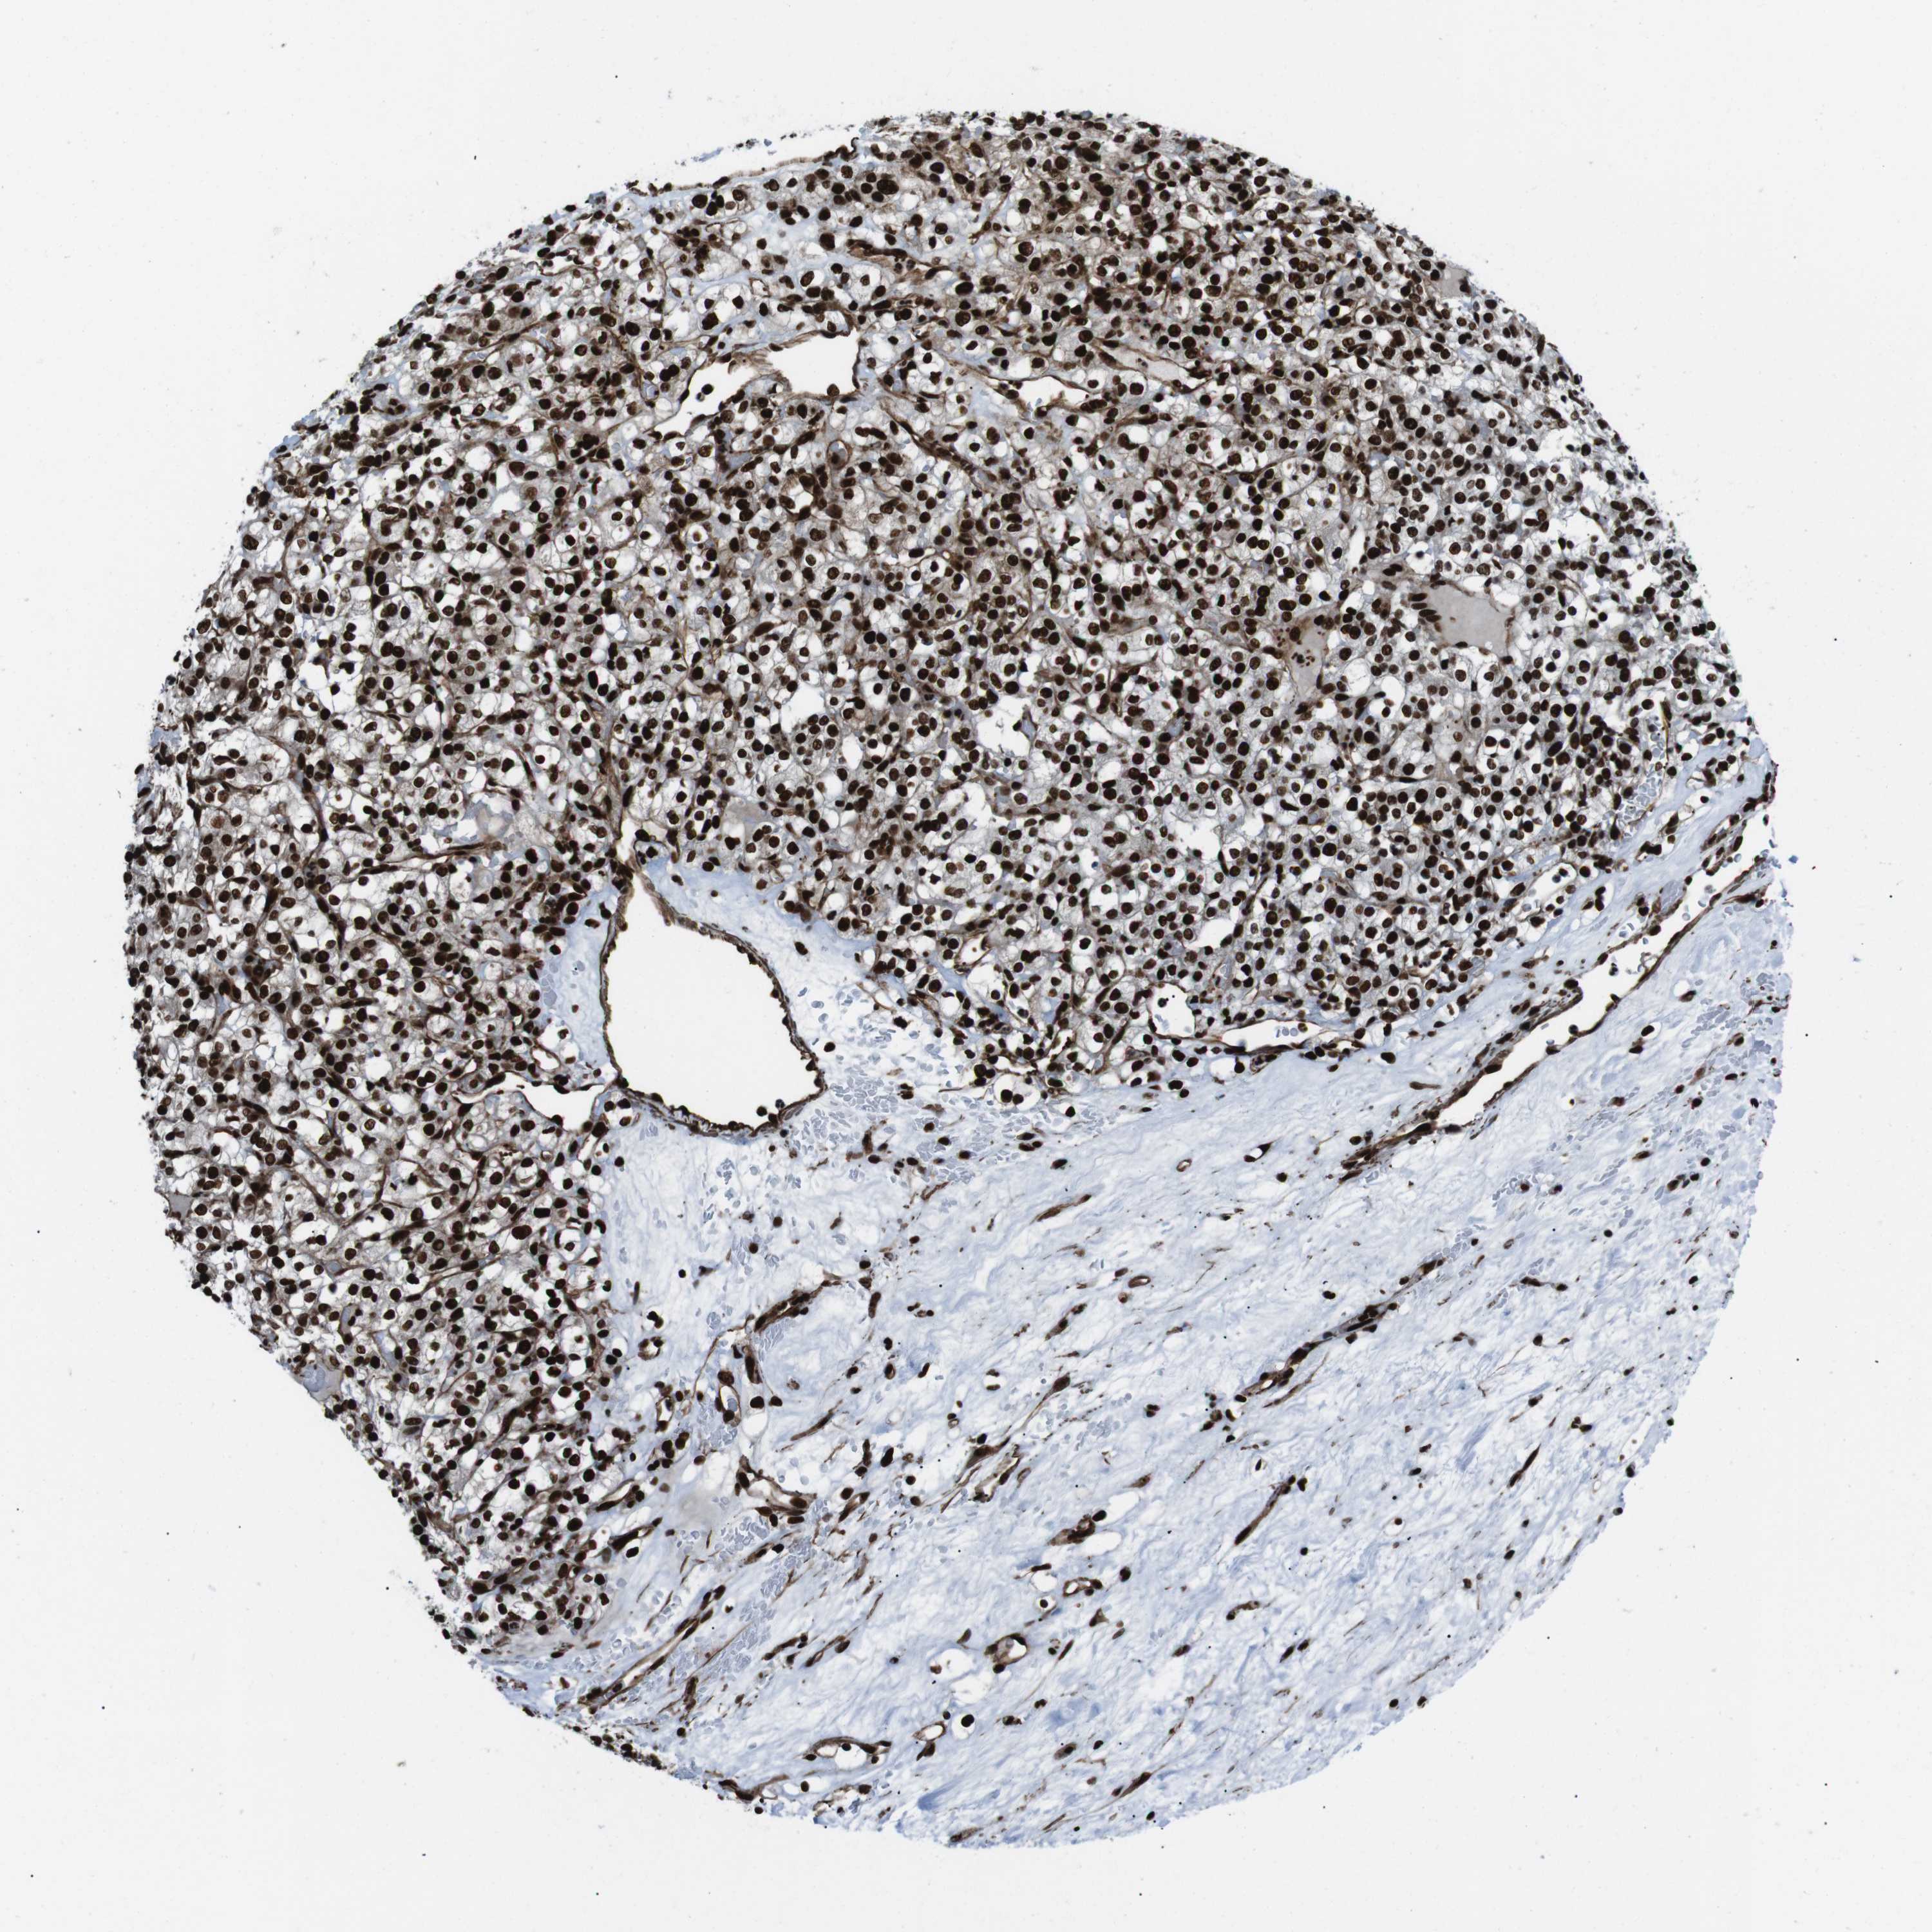

KIDNEY RENAL CLEAR CELL CARCINOMA (VALIDATION) - Interactive survival scatter ploti

The Survival Scatter plot shows the clinical status (i.e. dead or alive) for all individuals in the patient cohort, based on the same data that underlies the corresponding Kaplan-Meier plots. Patients that are alive at last time for follow-up are shown in blue and patients who have died during the study are shown in red.

The x-axis shows the expression levels (FPKM) of the investigated gene in the tumor tissue at the time of diagnosis. The y-axis shows the follow-up time after diagnosis (years). Both axes are complimented with kernel density curves demonstrating the data density over the axes. The top density plot shows the expression levels (FPKM) distribution among dead (red) and alive patients (blue). The right density plot shows the data density of the survived years of dead patients with high and low expression levels respectively, stratified using the cutoff indicated by the vertical dashed line through the Survival Scatter plot. This cutoff is automatically defined based on the FPKM cutoff that minimizes the p-score. The cutoff can be changed by dragging the vertical line or by entering a cutoff value in the square labeled "Current cut-off".

Under the Survival Scatter plot the p-score landscape (black curve; left axis) is shown together with dead median separation (red curve; right axis). Dead median separation is the difference in median mRNA expression between patients who have died with high and low expression, respectively. It is calculated as follows: median FPKM expression of dead patients with high expression - median FPKM expression of dead patients with low expression. This is intended to aid the user in visually exploring custom cutoffs and the associated p-scores and dead median separation.

Individual patient data is displayed and can be filtered by clicking on one or more of the category buttons on the top of the page. Categories describing expression level and patient information include: high, low, alive, dead, female, male and tumor stages. The scale of the x-axis can be toggled between linear and log-scale by clicking on the "x log" button. Mouse-over function shows TCGA ID, patient information and mRNA expression (FPKM) for each patient.

& Survival analysisi

Kaplan-Meier plots summarize results from analysis of correlation between mRNA expression level and patient survival. Patients were divided based on level of expression into one of the two groups "low" (under cut off) or "high" (over cut off). X-axis shows time for survival (years) and y-axis shows the probability of survival, where 1.0 corresponds to 100 percent.

HNRNPU is not prognostic in Kidney Renal Clear Cell Carcinoma (validation)

Best expression cut offi

Based on the FPKM value of each gene, patients were classified into two groups and association between prognosis (survival) and gene expression (FPKM) was examined. The best expression cut-off refers the FPKM value that yields maximal difference with regard to survival between the two groups at the lowest log-rank P-value. Best expression cut-off was selected based on survival analysis .

When clicking on this number, the vertical dashed line indicating cut-off, the interactive survival plot, and the Kaplan-Meier curve will be adjusted to show results based on the best expression cut-off.

: 133.42

Median expressioni

Median expression refers to the median FPKM value calculated based on the gene expression (FPKM) data from all patients in this dataset. When clicking on this number, the vertical dashed line indicating cut-off, the interactive survival plot, and the Kaplan-Meier curve will be adjusted to show results based on the median expression.

: N/A

Median follow up timei

Median follow up time refers to the median time (years) after diagnosis with this type of cancer, based on clinical data from all patients in this dataset.

P scorei

Log-rank P value for Kaplan-Meier plot showing results from analysis of correlation between mRNA expression level and patient survival.

N/A

5-year survival highi

5-year survival for patients with higher expression than the expression cutoff.

For melanoma and glioma, 3-year survival is shown.

5-year survival lowi

5-year survival for patients with lower expression than the expression cutoff.

TCGA RNA samplesi

RNA-seq data is reported as average FPKM (number Fragments Per Kilobase of exon per Million reads), generated by the The Cancer Genome Atlas (TCGA) .

Normal distribution across the dataset is visualized with box plots, shown as median and 25th and 75th percentiles. Points are displayed as outliers if they are above or below 1.5 times the interquartile range. FPKM values of the individual samples are presented next to the box plot.

Average pTPM 159.5

Number of samples 100